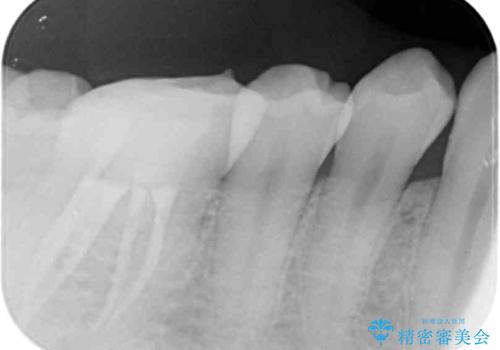

2. 放置してしまった虫歯の治療の治療中

2.